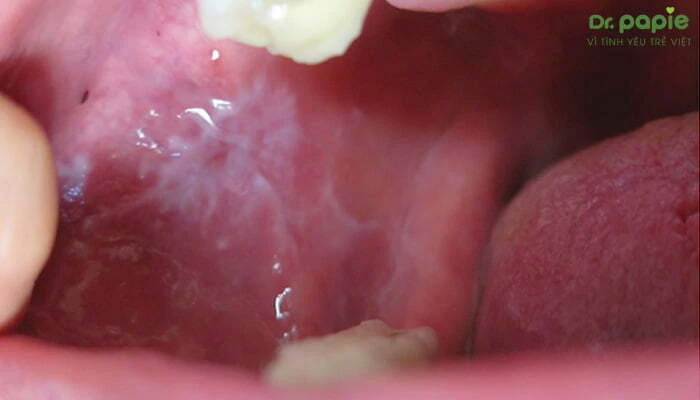

Nấm lưỡi là bệnh do nấm Candida Albicans ký sinh trong miệng. Đây cũng là nguyên nhân chính gây ra tình trạng trắng lưỡi ở trẻ sơ sinh. Loại nấm này có trong khoang miệng của trẻ, thường không gây hại. Nhưng nó lại có khả năng sinh sôi nhanh chóng và gây bệnh khi gặp các điều kiện thuận lợi như vệ sinh răng miệng kém, hệ miễn dịch của trẻ bị suy yếu, thường xuyên sử dụng thuốc kháng sinh hay sử dụng các thuốc corticosteroid …

Nấm lưỡi thường có các triệu chứng phổ biến như:

• Xuất hiện các đốm trắng như cặn sữa hoặc bông nổi trên bề mặt lưỡi của trẻ.

• Gây đau rát, đỏ, sưng tại vị trí lưỡi.

• Khô miệng, nứt nẻ môi và có vết nứt ở khóe miệng.